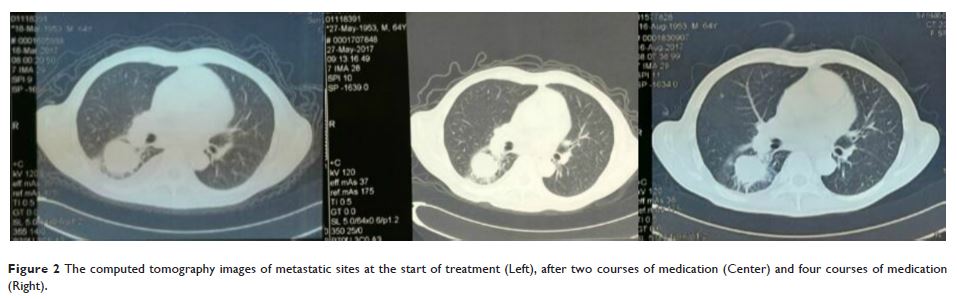

甲磺酸阿帕替尼片治疗常规化疗方案失败的晚期恶性黑色素瘤的临床效果观察